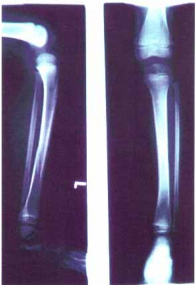

38 7 歲男童小銘,某日於公園騎腳踏車跌倒,導致左腿腫 脹疼痛不已,經送醫檢查發現其 X 光如右圖,則其診斷 應為下列何者?

(A)脛骨粗隆骨折 (B)脛骨幹骨折 (C)脛骨末端骨折 (D)距骨脫位